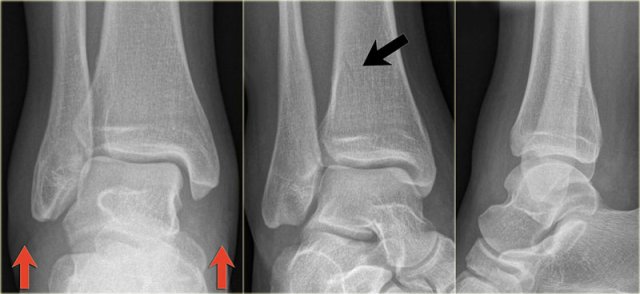

Example 2

• First impression

There is a fracture of the posterior malleolus.

Classification according to Weber is not possible.

An isolated fracture of the posterior malleolus is uncommon, but as part of a supination exorotation (Weber B) or pronation exorotation injury (Weber C) it is quite common.

So we have to re-examine the films to look for signs of a Weber B or C fracture.

• Re-examination

No sign of an oblique fracture of the lateral malleolus, so we can exclude a Weber B fracture.

There is still the possibility of a Weber C fracture, i.e. medial rupture or avulsion, high fibular fracture and finally a posterior malleolar fracture.

Now we notice the subtle avulsion of the medial malleolus (red arrow).

Additional radiographs of the lower extremity demonstrate a high fibular fracture (blue arrow).

• Final report

Weber C stage 4.